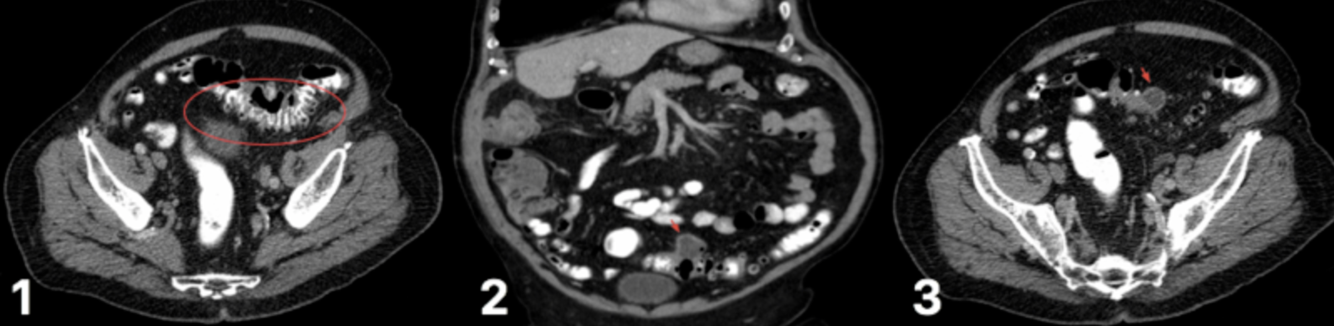

CT abdo-pelvis scan (thickening of the colonic wall, pericolonic fat stranding, abscesses, localised air bubbles, or free air; a “microperforation” is a radiologic diagnosis that reflects a localised perforation and inflammation)

CT scan for varying degrees of diverticular disease (1) diverticulum in the sigmoid colon (2) degree of diverticulitis present (3) abscess formation, secondary to ongoing diverticulitis